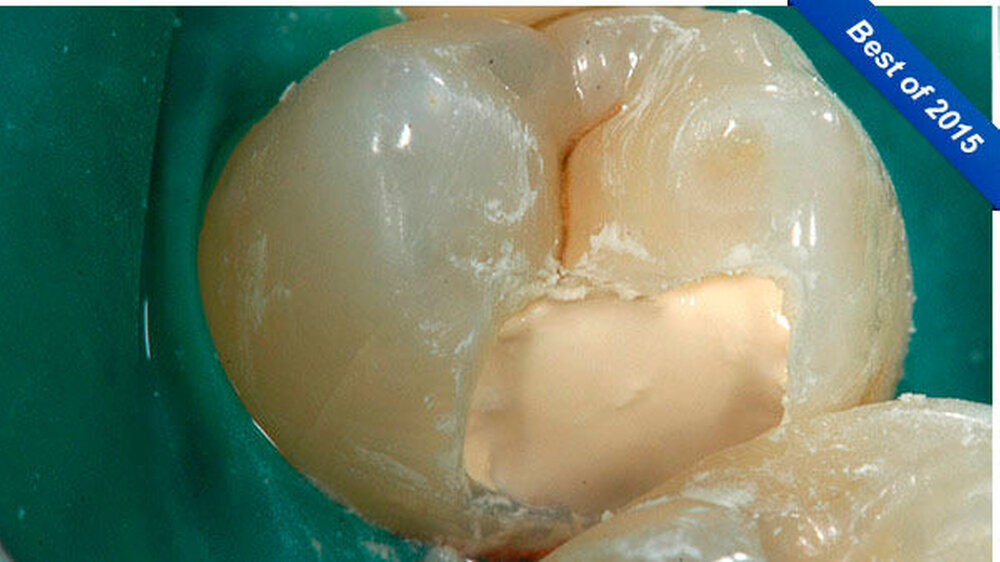

-Schnee positiv und in der Perkussionsprobe negativ. Nach ausführlicher Beratung des Patienten und Aufklärung über den Therapieablauf wurde eine terminale Infiltrationsanästhesie (Septanest, Septodont, Niederkassel) an Zahn 14 durchgeführt und Kofferdam gelegt (Abbildung 3). Nach Primärpräparation (Abbildung 4) kam es bei der vollständigen Exkavation der Dentinkaries zu einer iatrogenen Freilegung der Pulpa (Abbildung 5).

Klinisch stellte sich das Pulpagewebe als vital und ohne ausgeprägte Blutung dar, so dass zum Erhalt der Pulpavitalität eine direkte Überkappung in Betracht gezogen werden konnte. Zur Blutstillung sowie zur Reinigung und Desinfektion der Kavität wurde eine Kavitätentoilette mit NaOCl (2,5 Prozent) durchgeführt. Biodentine (Septodont, Niederkassel) wurde als Mittel für die direkte Überkappung ausgewählt. Der Zement wurde nach Herstellerangaben angemischt und sowohl auf das freiliegende Pulpagewebe als auch auf das Dentin im Sinne einer Unterfüllung appliziert (Abbildung 6).